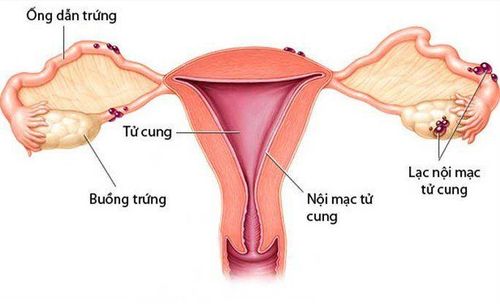

- Lạc nội mạc tử cung sâu, ảnh hưởng đến ruột, bàng quang và niệu quản.

- Lạc nội mạc tử cung ở buồng trứng.

Phẫu thuật lạc nội mạc tử cung nhằm loại bỏ lạc nội mạc tử cung và mô sẹo khỏi cơ thể bệnh nhân. Các phương pháp chẩn đoán và phẫu thuật nội soi bao gồm:

Nếu các vùng bị ảnh hưởng hoặc tổn thương nằm sâu trong cơ thể, bác sĩ có thể chỉ định phẫu thuật cắt bỏ khối u. Một số nghiên cứu cho thấy phương pháp này thường được chọn khi tình trạng lạc nội mạc tử cung đã chuyển biến trầm trọng hơn.

Trong quá trình phẫu thuật lạc nội mạc tử cung, bác sĩ có thể loại bỏ buồng trứng, ống dẫn trứng và tử cung (cắt tử cung) nếu các cơ quan này bị tổn thương và bệnh nhân không có ý định mang thai trong tương lai.